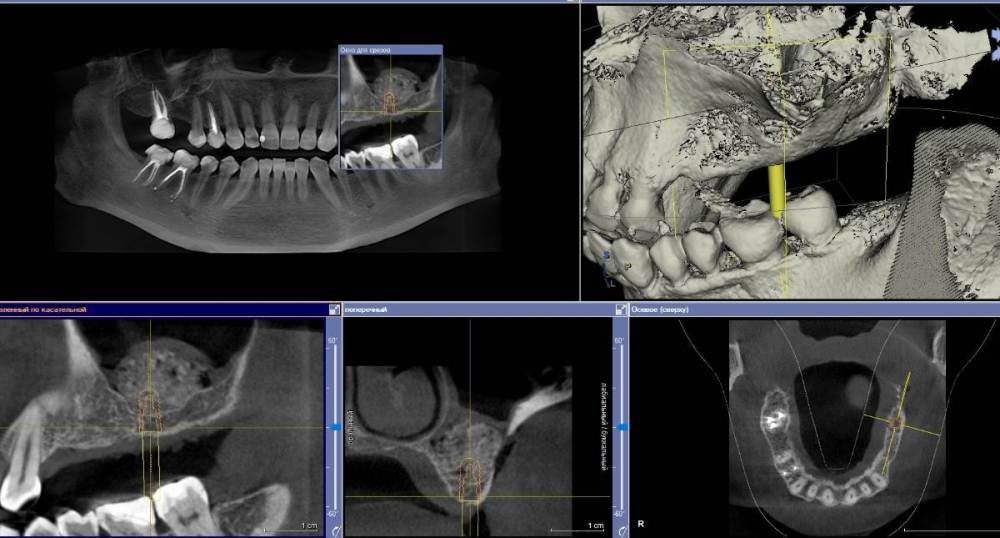

Ponchik Опубликовано 27 ноября, 2022 Поделиться Опубликовано 27 ноября, 2022 Неделю назад проведён синуслифтинг. Через 4-5 дней заболело горло. Вчера начался "НАСМОРК" Сегодня осмотр. Сделал КТ. Обработал местно антисептиками. Назначил Цефотаксим, Полидексу, Аквамарис (до этого был амоксиклав) отпустил до четверга. Вопрос: может зря я решил наблюдать? Надо было раскрыть и всё убрать? Просто растерялся. Первый раз за 6лет (как начал делать) синус проинфицировался. Ссылка на комментарий

Ponchik Опубликовано 27 ноября, 2022 Автор Поделиться Опубликовано 27 ноября, 2022 3 часа назад, TIGER сказал: @Ponchik дренаж работает?(соустье) Да. Работает. Отделяемое из носа есть и по кт видно как вся эта куча графта, с» и жидкости тянется к соустью. Срез просто выбран по середине графта в зоне операции. Вопрос второй назрел. Кто виноват? Всё закисло на первой неделе. Лоскут лежит вроде нормально. Можно считать инфицирование произошло во время операции? Грешить на обработку поля, рук и инструментов? Или? Пациент очень боялся именно такого исхода. Я выдал больничный и человек старался из дома нос не высовывать. Ссылка на комментарий

АнтонТЛТ Опубликовано 27 ноября, 2022 Поделиться Опубликовано 27 ноября, 2022 Сморкался скорее всего) вообще проблемы не вижу. Графта свыше крыши, что останется должно хватить для имплантации. У меня только один вопрос по тактике, почему сразу имплантация не была проведена? Если на этапе имплантации увидите, что в синусе графт не интегрировался, то убрать его и засыпать новый. 1 Ссылка на комментарий